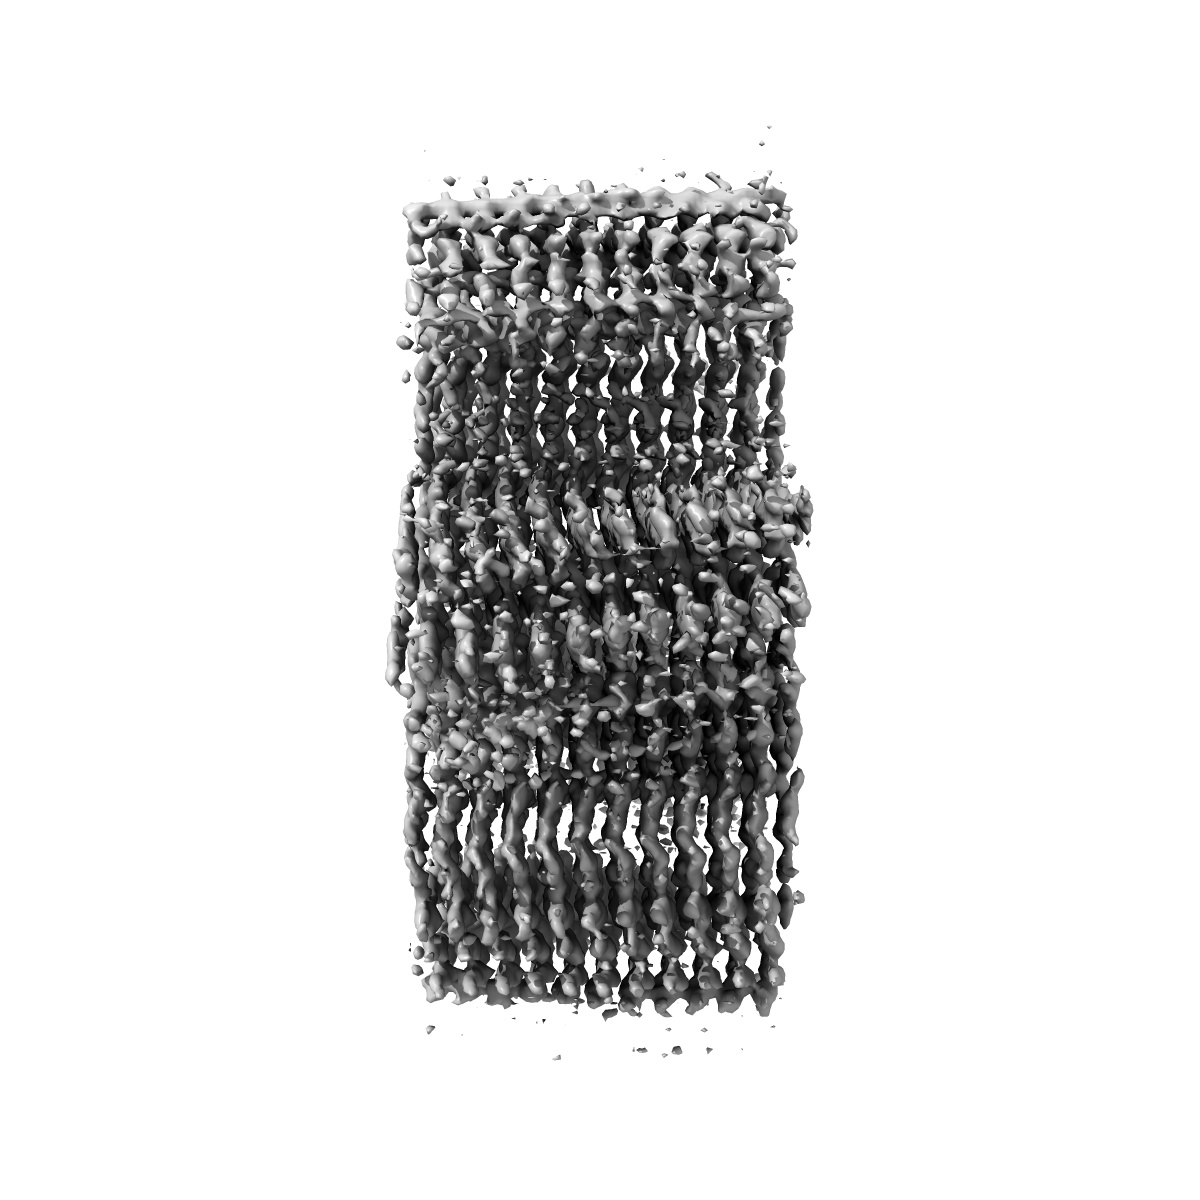

Straight Filaments purified from Down Syndrome individual brain tissue applied to graphene oxide antibody affinity grids

Cryo-EM structures reveal tau filaments from Down syndrome adopt Alzheimer's disease fold.

Ghosh U, Tse E, Yang H , Shi M, Caro CD, Wang F, Merz GE, Prusiner SB, Southworth DR, Condello C

(2024) Acta Neuropathol , 12 , 94 - 94